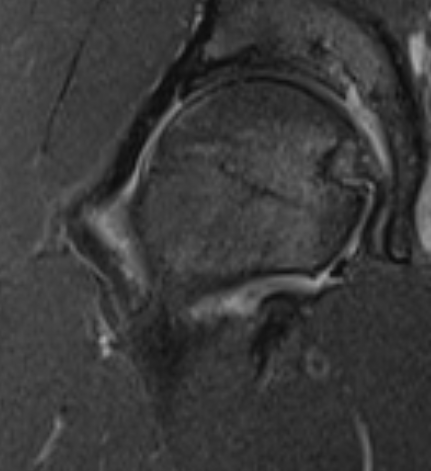

T2 Double Line Sign

Two lines virtually diagnostic of AVN

- outer line / low signa intensity

- inner line / high signal intensity / hypervascular granulation tissue